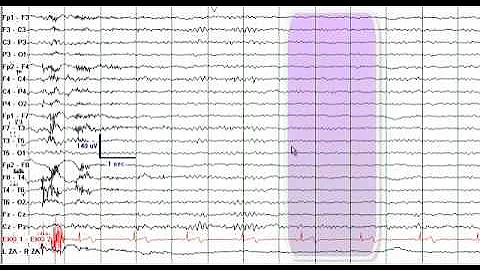

I review an EEG from a patient with Temporal Lobe Epilepsy.